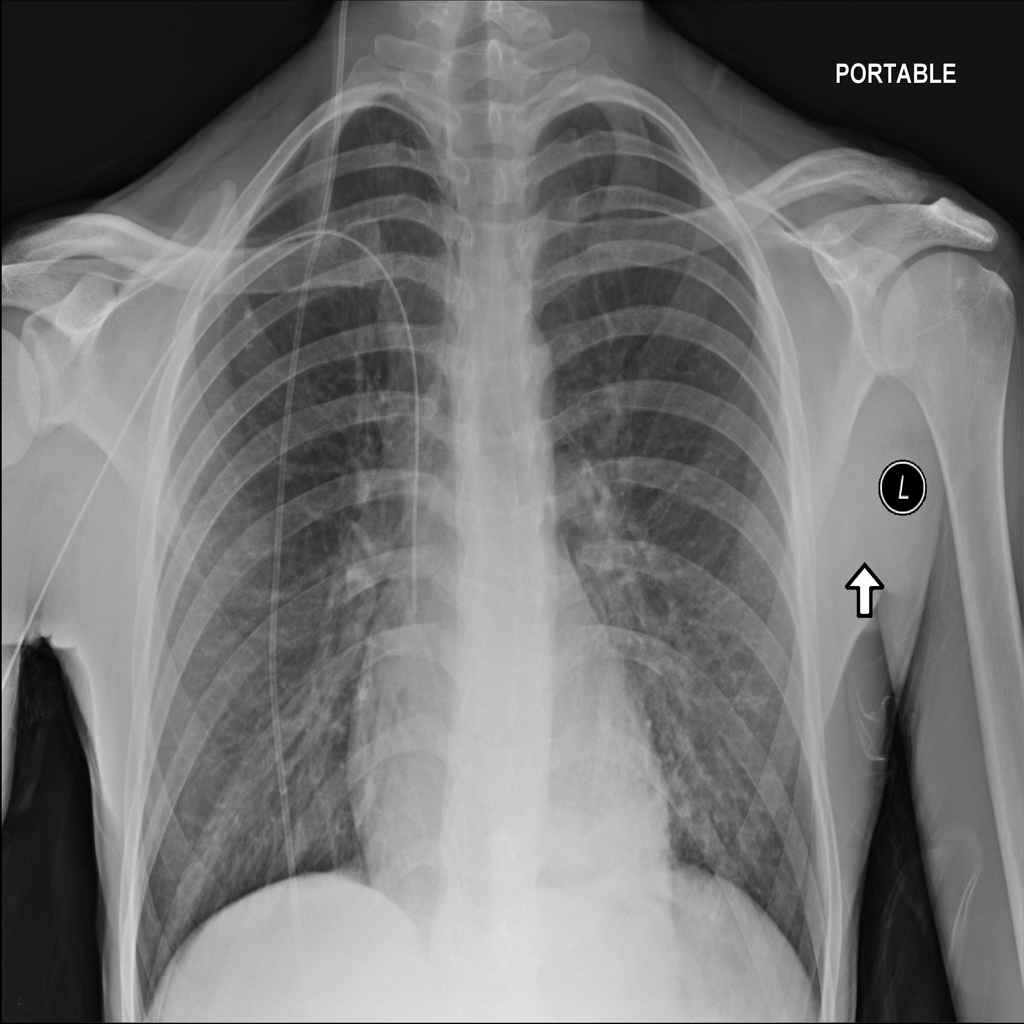

PAT-285F · IMG-000Consolidation

PAT-285F · IMG-000

PA